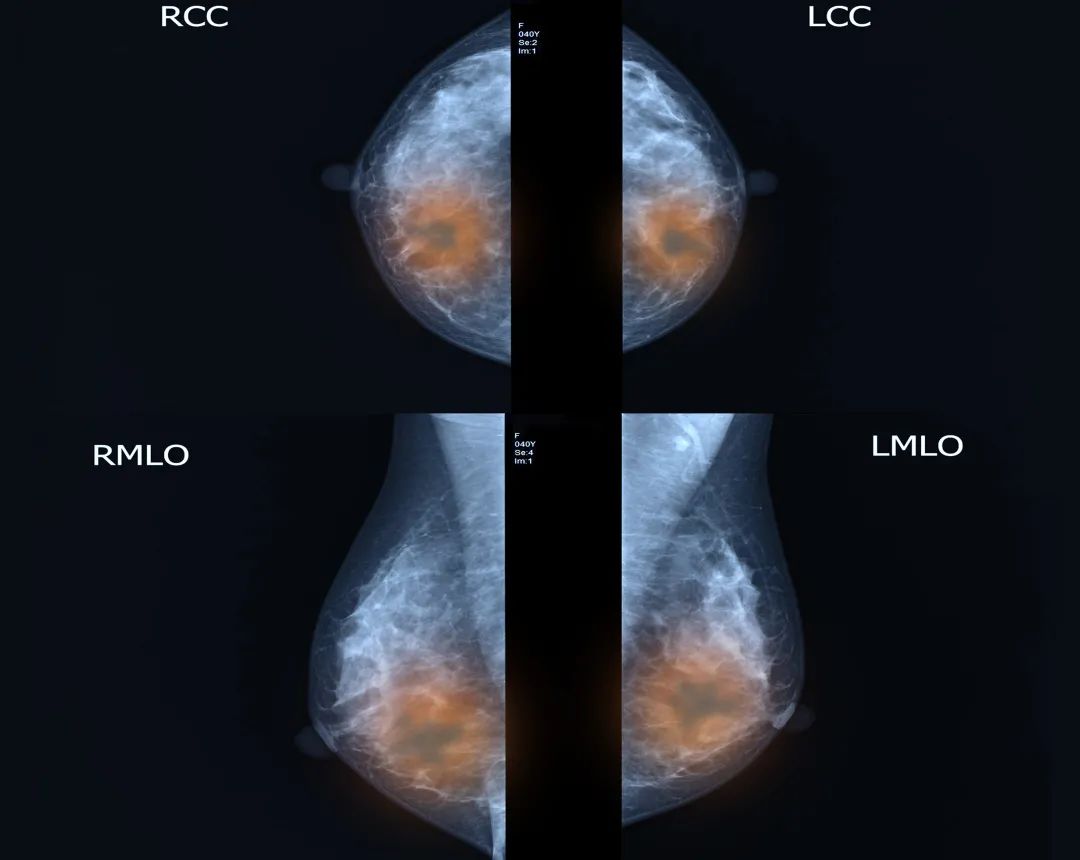

下图是一位乳腺癌患者的乳腺钼靶X线检查的图像

▼